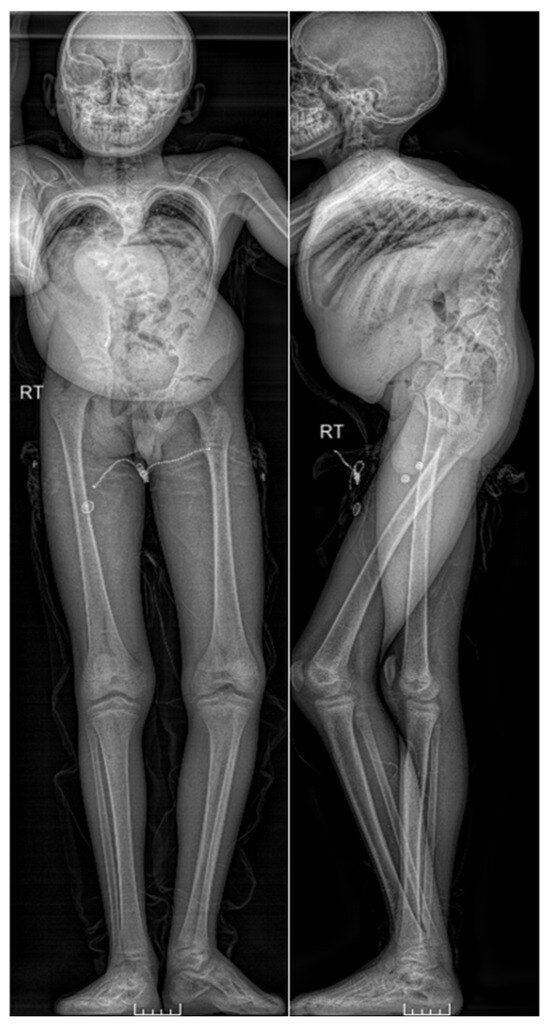

Figure 2.

Full length AP and lateral EOS images taken pre-operatively.

A 14-year-old African male with congenital scoliosis, managed non-operatively since initial diagnosis at age 3 years, complained of pain while walking or lying down but no radicular complaints or bowel or bladder issues. He had previously been hospitalized due to radiating pain in his spine at about 6 years old, but has had no additional hospitalizations since then. He was small in stature with an obvious deformity and coronal imbalance (Figure 1 and Figure 2). Neurologic exam revealed full motor strength with no sensory deficits or myelopathic signs.